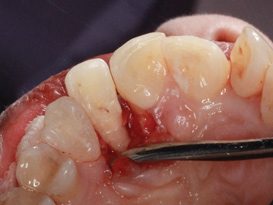

(1.) Pretreatment occlusal view showing crowding and inflamed palatogingival groove of tooth No. 7.

Figure 1

A 45-year-old female patient was referred to our office for the treatment of bleeding gums and sensitivity associated with tooth No. 7. Clinical and radiographic evaluations revealed highly inflamed tissues, easily provoked bleeding, and edematous palatal gingival tissue supporting tooth No. 7 (Figure 1 and Figure 2). Crowding, a widened periodontal ligament, dens in dente, deep probing depths, bleeding on probing, dilacerations, missing papilla, and angular bone loss were also observed, indicating that tooth No. 7 had a poor prognosis. The groove began at the cingulum and formed a deep fold of enamel that extended to the coronal third of the root. This radicular groove disrupted normal periodontal attachment and caused a self-sustaining, progressive localized periodontal pocket to form. The groove also presented a potential pathway for bacterial penetration into deeper parts of the root, which could lead to endodontic involvement if left untreated.6